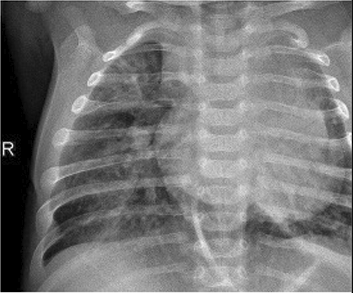

Table 6 Fused image output.

From: Multimodal medical image fusion combining saliency perception and generative adversarial network